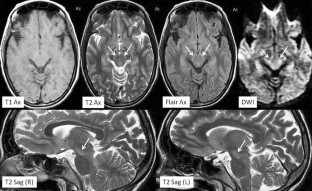

Fig. 1